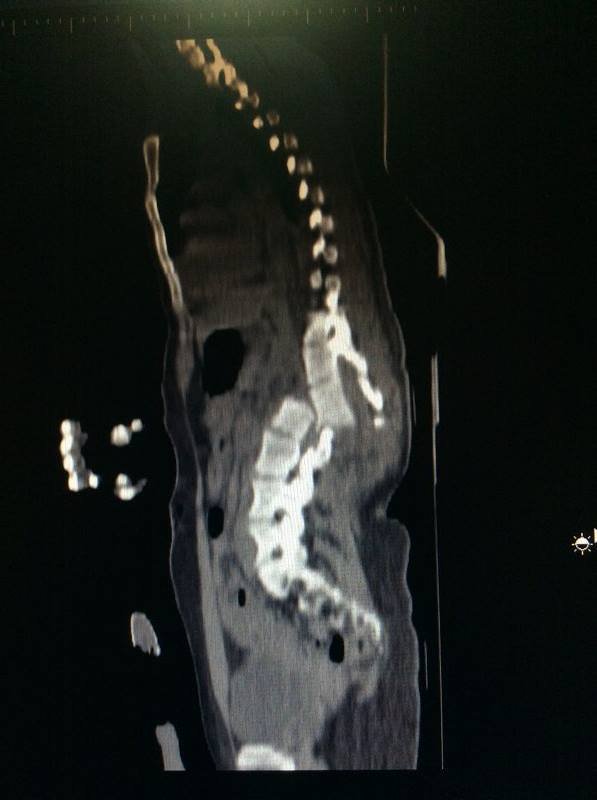

"Сьогодні, нарешті без такої паніки та жаху змогла глянути на свої знімки, це мої знімки після аварії. Чесно кажучи, ні у мене, ні у лікарів немає слів і розуміння, як я взагалі залишилася живою і ще ЖИВУ".

"Є певний страх і сумніви стосовно того, як пройде операція і чи буде вона успішною, адже, окрім зламаної ключиці, 5 ребер зліва і 2 справа та забою серця і спинного мозку маю ще складну травму хребта над якою і будуть працювати спеціалісти, які погодилися взятися за цю операцію," - розповідає дівчина.